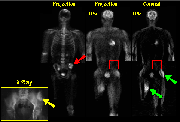

Whole-body 18F- scans are useful for the detection of bone tumors as well as for studying the progression of these tumors over time. 18F- is particularly suited for the study of bone tumors because it is readily incorporated into bone. Regions displaying increased 18F- incorporation (e.g., arrows) are indicative of tumor formation.